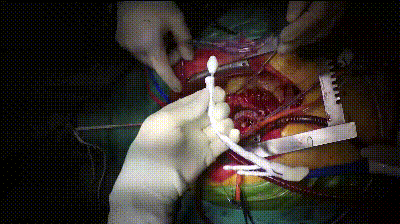

剪除部分覆膜支架及左锁骨下烟囱支架

植入术中单分支支架

术中单分支支架开窗及加固